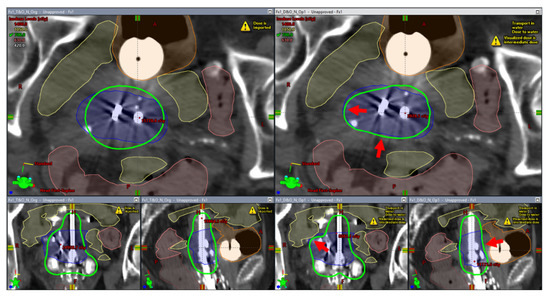

2.2. A Patient Example